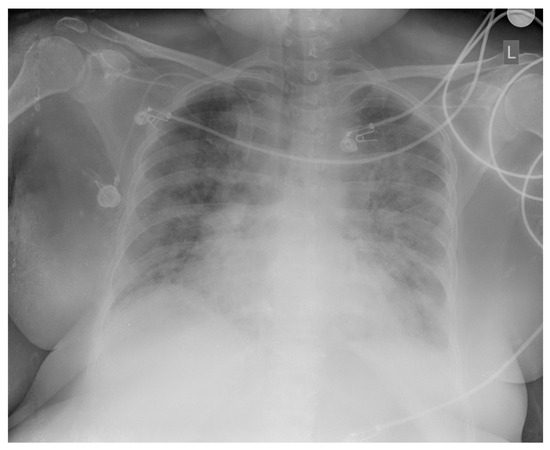

2. Case Presentation